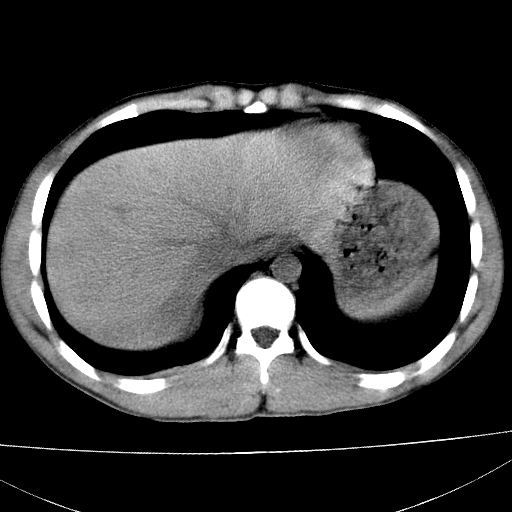

标题: CT15860:男,21岁,腹部外伤2小时伴胸疼。 [打印本页]

标题: CT15860:男,21岁,腹部外伤2小时伴胸疼。

b超示:肝破裂。

肝脏及肾脏明显有损伤性改变并激发腹腔内积液(血),以肝脏撕裂及肾周积血显著。

1)肝破裂伴腹腔积液(血)。2)右肾破裂伴右肾包膜下及肾周血肿。3)腹部空腔脏器穿孔可能。4)右侧少量胸腔积液(血)。

1)肝破裂伴腹腔积液(血)。2)右肾破裂伴右肾包膜下及肾周血肿。3)右侧少量胸腔积液(血)。

肝、右肾包膜下血肿,右侧腰大肌及腹膜后血肿;腹腔少量积血;腹腔疑有少量游离气体伴肠破裂。

1肝挫伤伴腹腔积液。2右肾挫裂伤伴右肾包膜及肾后间隙肿血肿。3右肾脏周围的积气,十二指肠显示结构不清,考虑十二指肠降部破裂可能性大。